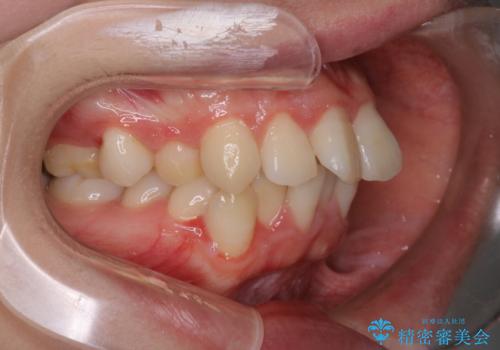

【抜歯インビザ】凸凹を綺麗になおしたい

- 前歯の凸凹を主訴に来院されました。

叢生量が多いため、抜歯が必要となるため、ワイヤー矯正をお勧めしましたが、患者さんの希望によりインビザラインで治療を開始しました。途中でワイヤーリカバリーを必要とせず終了でき患者さんには満足していただけました。